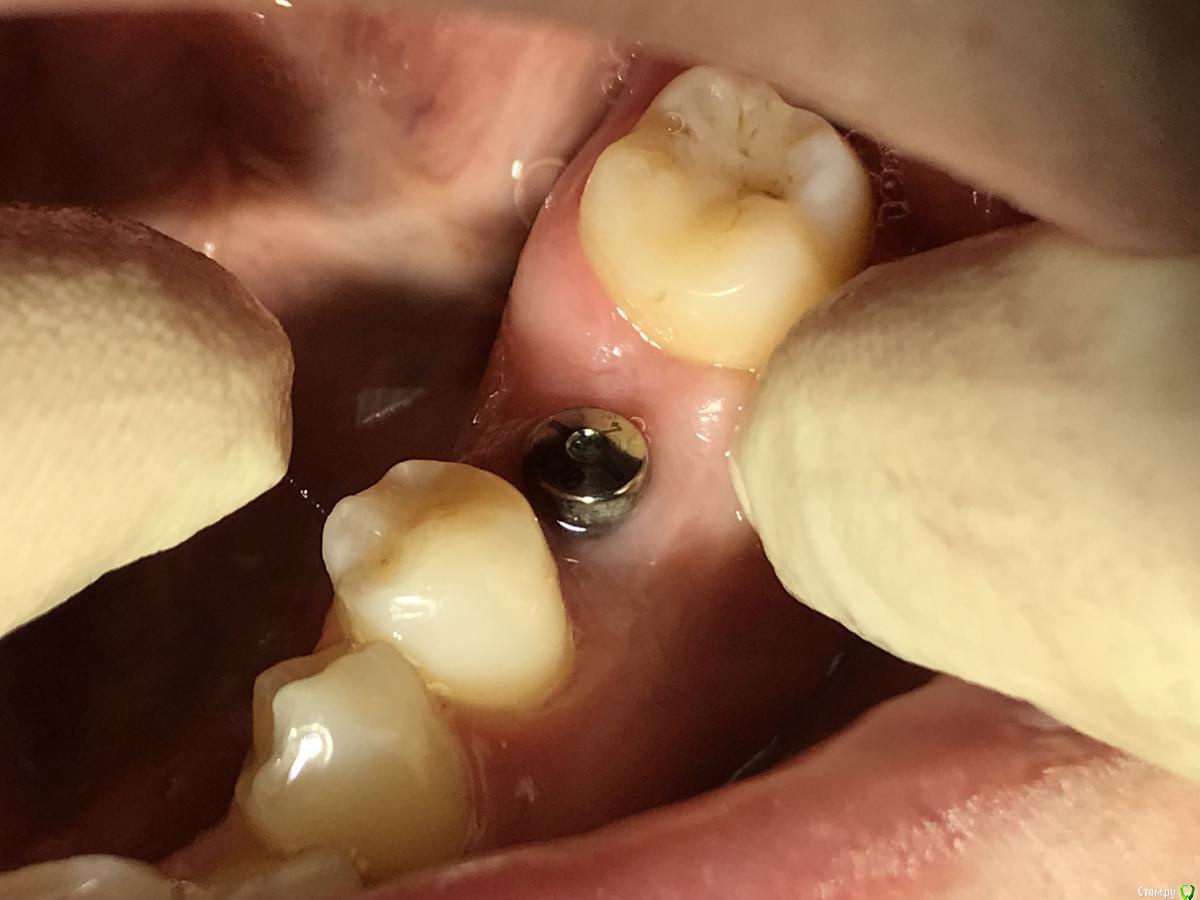

El_cucuy Опубликовано 22 января, 2020 Поделиться Опубликовано 22 января, 2020 (изменено) 1) поставить низкую заглушку, подшить сверху трансплантат под лоскутки 2) не делать ничего до интеграции, решать вопросы на втором этапе Доброго времени суток , доктора . По состоянию на 20 декабря , вот такая картина , нужно ли подсаживать трансплантат? Изменено 22 января, 2020 пользователем El_cucuy Ссылка на комментарий

El_cucuy Опубликовано 22 января, 2020 Поделиться Опубликовано 22 января, 2020 (изменено) нужны фото. И создавайте свои темы, а не засоряйте чужиеТот же кейс , добавил спустя 2 месяца Изменено 22 января, 2020 пользователем El_cucuy Ссылка на комментарий

red_butler Опубликовано 22 января, 2020 Поделиться Опубликовано 22 января, 2020 Ранее не было аккаунта , коллега мой закидывал , зарегестрировался сегодняок, фото во рту покажите 1 Ссылка на комментарий

El_cucuy Опубликовано 26 января, 2020 Поделиться Опубликовано 26 января, 2020 и? Ссылка на комментарий

Дмитрий Л. Опубликовано 26 января, 2020 Поделиться Опубликовано 26 января, 2020 Я бы не подсаживал, вроде 3 мм есть. 1 Ссылка на комментарий

red_butler Опубликовано 26 января, 2020 Поделиться Опубликовано 26 января, 2020 не вижу смысла работать с десной Ссылка на комментарий